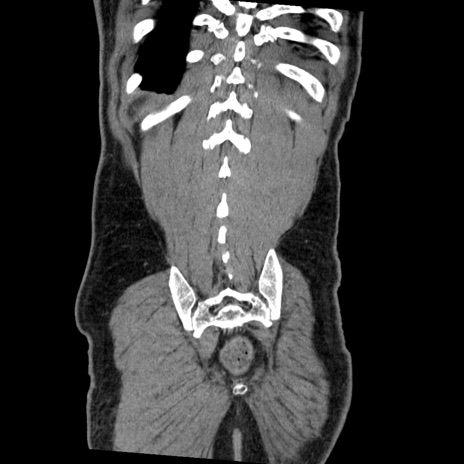

横断像